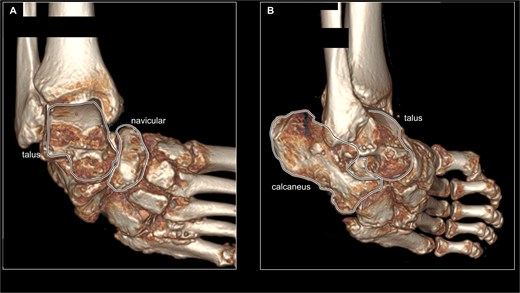

Preoperative radiographs demonstrated marked varus deformity of the ankle and abnormal weight-bearing on the lateral border of the foot (Fig. 2A and B). Under valgus stress, correction of the ankle and subtalar deformities was possible, but the midfoot inversion remained uncorrectable (Fig. 2C). Computed tomography revealed midfoot inversion associated with talonavicular subluxation (Fig. 3A and B). Based on these findings, surgical treatment aimed at achieving a plantigrade foot and restoring ambulation was planned.

Preoperative CT imaging of the right foot. (A) 3D reconstructed image of preoperative CT scan from ankle joint frontal view. The talus and navicular bones are surrounded by black lines, showing subluxation of the talonavicular joint. (B) 3D reconstructed image of preoperative CT scan from ankle joint anterolateral view. The talus and calcaneus are surrounded by a black line, showing marked varus deformity of the subtalar joint.